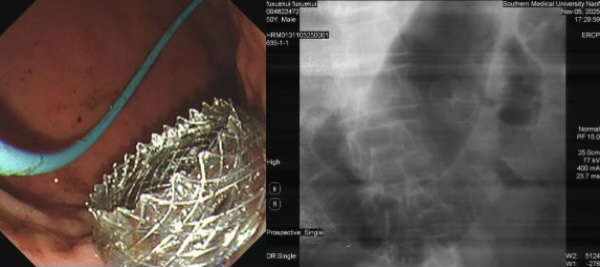

面对这一困难,罗晓蓓博士团队决定迎难而上,采用一项国内前沿技术——超声内镜引导下胃肠吻合术(EUS-GE)。这项手术技术壁垒极高,要求术者在内镜和超声的双重引导下,精准穿刺胃壁与空肠,并植入支架建立“消化道立交桥”,稍有不慎就可能导致严重并发症。为确保手术安全顺利,消化内科主任医师顾红祥教授全程提供指导。

为创造安全的手术条件,手术前,医疗团队用了一个半小时进行了极其细致的洗胃和胃内食物残渣清理工作。随后的EUS-GE操作仅用时十余分钟,在超声胃镜与X线的精准引导下,团队成功经胃体实施了胃空肠吻合支架植入,巧妙绕开了肿瘤梗阻区域,手术取得圆满成功。

术后患者梗阻症状迅速解除,效果立竿见影,目前已顺利恢复经口进食,生活质量得到极大地改善。“真的特别医护团队的精湛医术和辛勤付出,能够重新经口吃饭喝水,感觉像个正常人一样,什么都好了!”患者和家属感慨道。